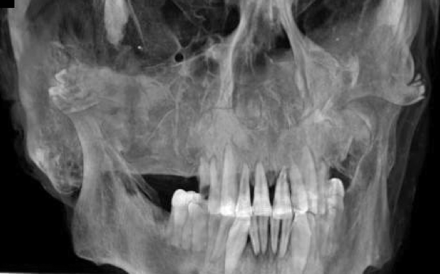

Dentition.

There are 15 mandibular teeth (Fig 12). The last mandibular molar on the right (ADA 32) has been removed, and the socket for this molar is visible. All 3 of the molars on the left are intact.

A slightly oblique view of the dentition.

The middle 10 maxillary teeth are present. These include the middle and lateral incisors, the canines, and the 2 premolars, bilaterally. The second premolar on the left is partially fractured. A periapical lucency in the left central incisor in the maxilla may represent dental disease or may be an artifact of postmortem dental trauma during preparation.

There is a dense object just inferior to the right nasal opening and anterior to the maxillary alveolar ridge that may be a broken tooth or a bone fragment. It appears to be on the skin surface beneath the linen, rather than subcutaneous or intraoral.